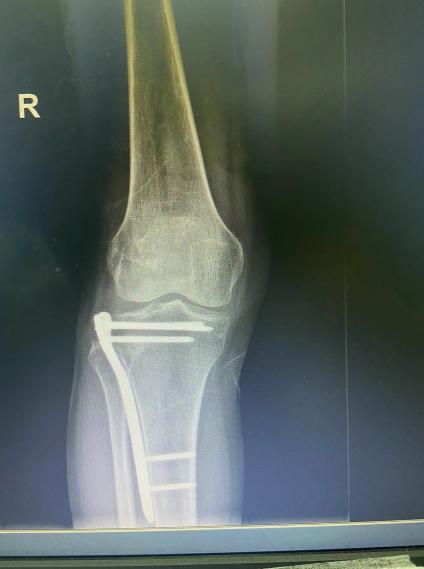

考虑传统手术前外侧大切口需要劈开外侧平台造成一个人为骨折从而显露塌陷关节面,复位后再用钢板固定人为造成的胫骨外侧平台骨折,手术创伤大,术后关节功能影响较大。

传统切口

传统内固定钢板